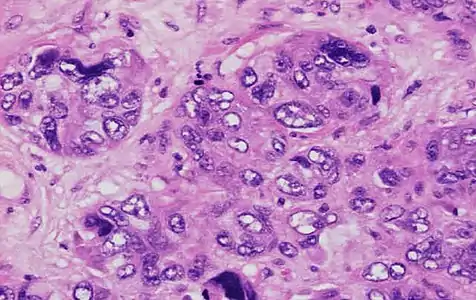

Invasive ductal carcinoma with marked nuclear pleomorphism.

Nuclear pleomorphism

This parameter assesses whether the cell nuclei are uniform like those in normal breast duct epithelial cells, or whether they are larger, darker, or irregular (pleomorphic). In cancer, the mechanisms that control genes and chromosomes in the nucleus break down, and irregular nuclei and pleomorphic changes are signs of abnormal cell reproduction.

Note: The cancer areas having cells with the greatest cellular abnormalities should be evaluated.

- 3 points: nuclei with marked variation in size and shape